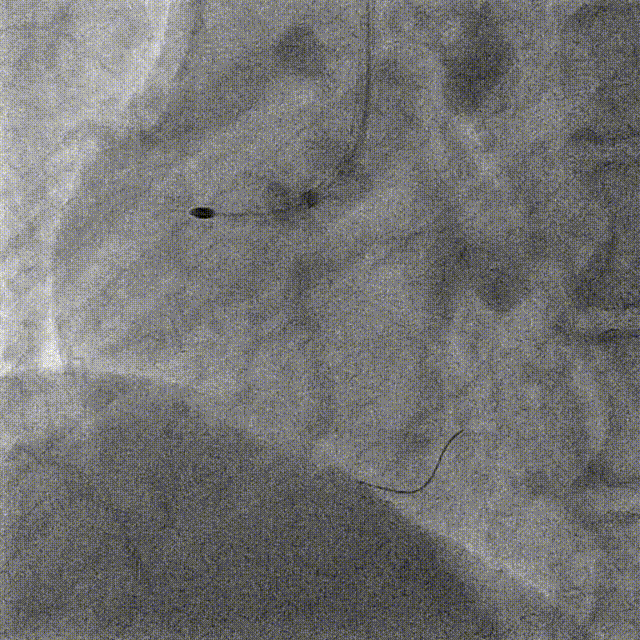

DES Deployment & Optimization DES 4.0*20mm → NC 4.0*12mm @ 20atm

Stenting DES 2.5*24mm

Stent Optimization NC 2.5*12mm + NC 2.75*8mm

Lesion Preparation Cutting balloon 2.75*10mm @ 14atm

DCB Angioplasty DCB 2.75*25mm @ 8atm, 60s